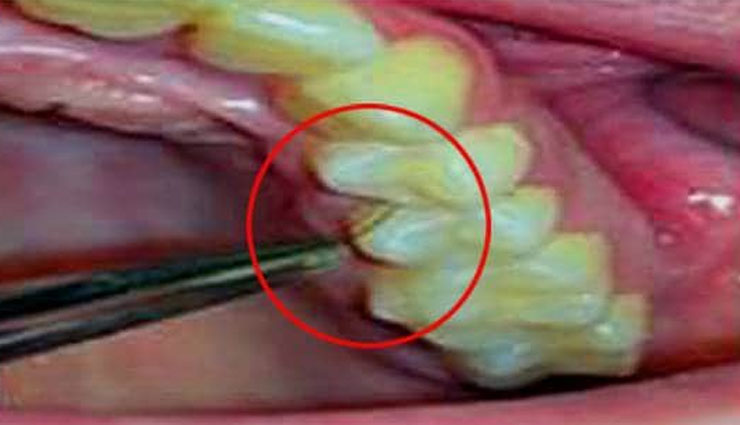

हमारे हाथ या पैर पर उगे बालों से हमें कोई परेशानी नहीं होती। लेकिन अगर हमारे मुंह में बाल उगने लग जाए तो हालत खराब हो जाती है। ऐसा ही कुछ हुआ इटली की एक महिला के साथ। महिला के मुंह में दांतों और मसूड़ों में बाल निकल रहे है। इटली की एक 25 वर्षीय युवती के मुंह में दांतों और मसूड़ों के बीच बाल उग आए हैं। दांतों और मसूड़ों ये एक बेहद दुर्लभ बायोलॉजिकल स्थिति है। इसे लेकर डॉक्टर भी हैरान हैं। डॉक्टरों के समझ में ये नहीं आ रहा है कि इसके पीछे कारण क्या है?

इटली के डॉक्टरों का मानना है कि इसके लिए पॉलीसिस्टिक ओवरी सिंड्रोम नामक दुर्लभ बीमारी जिम्मेदार हो सकती है। कुछ डॉक्टर इसे गिंगिवल हर्सुटिज्म (Gingival Hirsutism) बीमारी भी बता रहे हैं। इसमें शरीर के ऐसे हिस्सों में बाल उग आते हैं जहां नहीं होने चाहिए। हालांकि अभी तक इसका सही कारण डॉक्टर पता नहीं कर पाए हैं।

इटली की जिस महिला के मुंह के अंदर दांतों और मसूड़ों में बाल निकले हैं उसे 15 साल की उम्र में टेस्टोस्टेरोन ज्यादा होने की दिक्कत सामने आई थी। लेकिन उसका इलाज हो चुका है। डॉक्टरों ने अब उसके मसूड़ों के के ऊतकों की जांच भी की लेकिन कोई कारण पता नहीं चल पा रहा है।

यह पहली बार है जब किसी महिला को यह बीमारी हुई है। इसके पहले दुनिया में इस बीमारी से ग्रसित पांच पुरुष ही हैं। इन पुरुषों के मुंह के अंदर दांतों और मसूड़ों के बीच भी बाल उग आए थे।

डॉक्टरों का अभी तक यही मानना है कि यह महिला गिंगिवल हर्सुटिज्म से पीड़ित है। इस बीमारी और इससे पीड़ित लोगों के बारे में एक विशेष रिसर्च रिपोर्ट ओरल पैथोलॉजी जनरल में हाल ही में प्रकाशित हुई है।